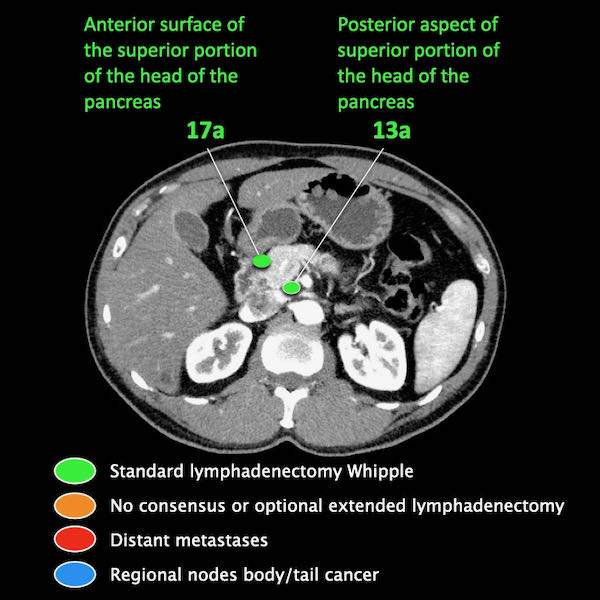

Trong hình minh họa này, chúng tôi sử dụng các trạm hạch bạch huyết trong ung thư tụy theo đề xuất của Hội Tụy học Nhật Bản.

Các chặng hạch bạch huyết trong ung thư tụy

Các chặng hạch bạch huyết trong ung thư tụy theo đề xuất của Hội Tụy học Nhật Bản.